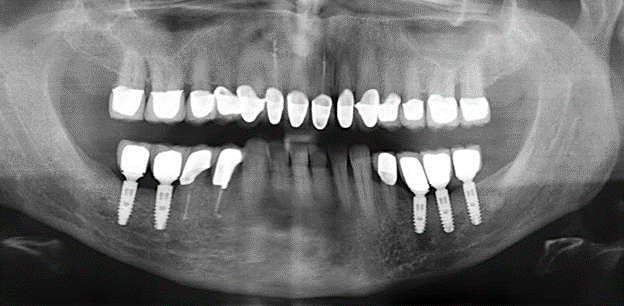

Un paziente di 52 anni si è presentato nella nostra clinica per la prima volta nel 2004 a seguito della perdita dei denti nel terzo quadrante, esprimendo il desiderio di un nuovo restauro protesico. La diagnostica parodontale e radiologica ha rivelato la necessità di un ampio trattamento parodontologico. Inoltre, ai denti 48, 28 e 27 è stata attribuita una prognosi molto scarsa e sono stati successivamente estratti (Fig. 1). A seguito del trattamento periodontologico sistematico completato con successo, è stato inserito una protesi dentale fissa con l'inserimento di cinque impianti nelle regioni dentali 35, 36, 37, 46 e 47. Il trattamento protesico dei denti naturali è stato effettuato con corone rivestite in ceramica di biossido di zirconio; gli impianti two-piece composti da abutment singoli in biossido di zirconio e corone similmente rivestite in ceramica di biossido di zirconio (base Cercon colorata, Dentsply Sirona Lab). L'inserimento definitivo del restauro protesico è avvenuto nel 2005.

A causa della presenza di problematica parodontale, SPT è stata eseguita ogni tre mesi nei primi anni successivi all'inserimento. Il paziente ha dimostrato un alto grado di motivazione e una buona costanza. Le profondità di tasca registrate ogni anno hanno rivelato una situazione parodontale stabile con un indice BOP inferiore al cinque per cento. Sulla base della situazione parodontale stabile e della buona collaborazione da parte del paziente, l'intervallo di richiamo è stato esteso ogni sei mesi a partire dal sesto anno dalla fase della funzione protesica. A seguito della modifica dell'intervallo di richiamo, la rispettiva documentazione annuale dello stato parodontale ha continuato a rivelare una situazione parodontale stabile senza aumento della profondità della tasca e un indice BOP inferiore al cinque per cento (Fig. 2a eb).

Il controllo decennale non ha rivelato alcuna indicazione dell'avanzamento della perdita di attaccamento clinico o della perdita di sostanza ossea perimplantare (Fig. 3).